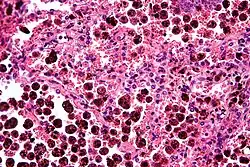

Micrograph of carbon-laden macrophages in the lung, H&E stain